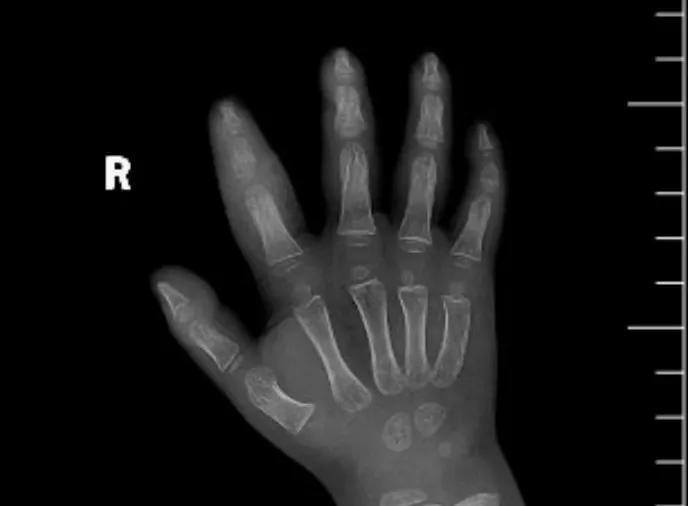

近日,市二院顯微外科接診一名3歲半的小患者,被玉米葉割傷右食指,因家長疏忽大意,導(dǎo)致一個(gè)小小的傷口竟然發(fā)展成了骨髓炎。來院時(shí)患兒右食指腫脹明顯,既不能伸也不能彎,皮膚發(fā)燙,疼得哇哇大哭。

第三天開始,月月哭鬧不止,一直說手疼,怎么哄也不行,于是在當(dāng)?shù)蒯t(yī)院治療了10來天,然而月月的手指依然腫得像個(gè)胡蘿卜,疼痛感依然存在。此時(shí),月月的媽媽才覺得事情不大對(duì)勁,于是經(jīng)過打聽,慕名來到市二院顯微外科。入院后,經(jīng)檢查發(fā)現(xiàn),月月的右食指骨質(zhì)有侵蝕,骨骺有缺損,甚至?xí)绊懸院笫种傅陌l(fā)育。聽到這個(gè)消息,月月媽媽感覺心都揪住了。

隨后,經(jīng)顯微外科團(tuán)隊(duì)充分的討論,制定了科學(xué)細(xì)致的治療方案,為月月做了感染灶清除及手指的開放引流,并留取了標(biāo)本做細(xì)菌培養(yǎng),為進(jìn)一步的合理用藥提供依據(jù)。經(jīng)過兩周的治療,月月的手指終于順利消腫愈合,并且手指功能活動(dòng)良好。說起這一個(gè)多月的煎熬,月月媽媽不禁落淚,但總算是治愈了,笑容又重新回到她們一家的臉上。